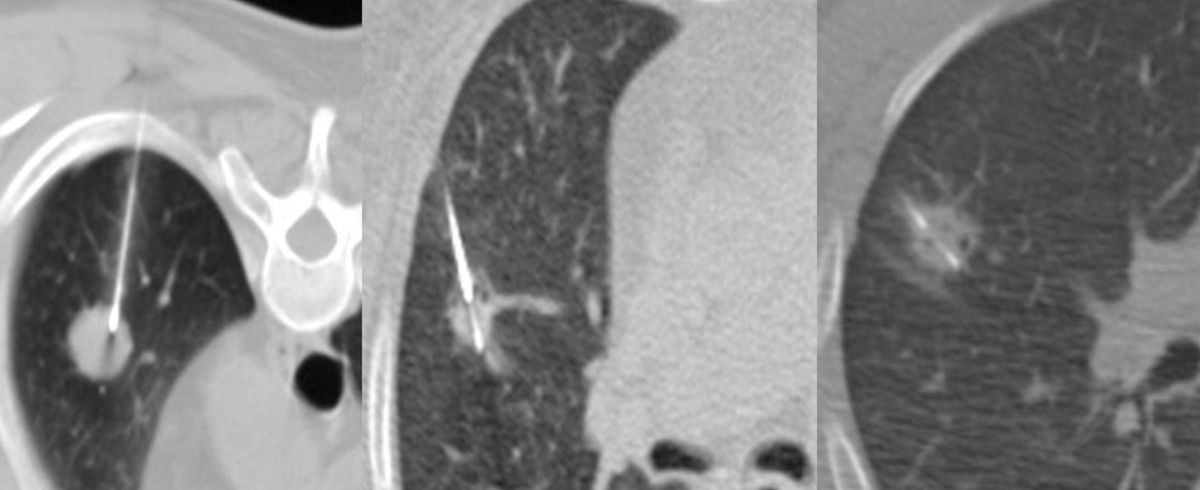

The patient was referred for a CT guided biopsy.

The only approach is anterior in this case (Fig. 2). A posterior approach, though possible in any instances, is difficult in her because of the anatomy, unless you go transvertebral.

Fig. 3 shows the AP diameter. The posterior margin has a vein draining into the IVC, so care has to be taken not to overshoot.